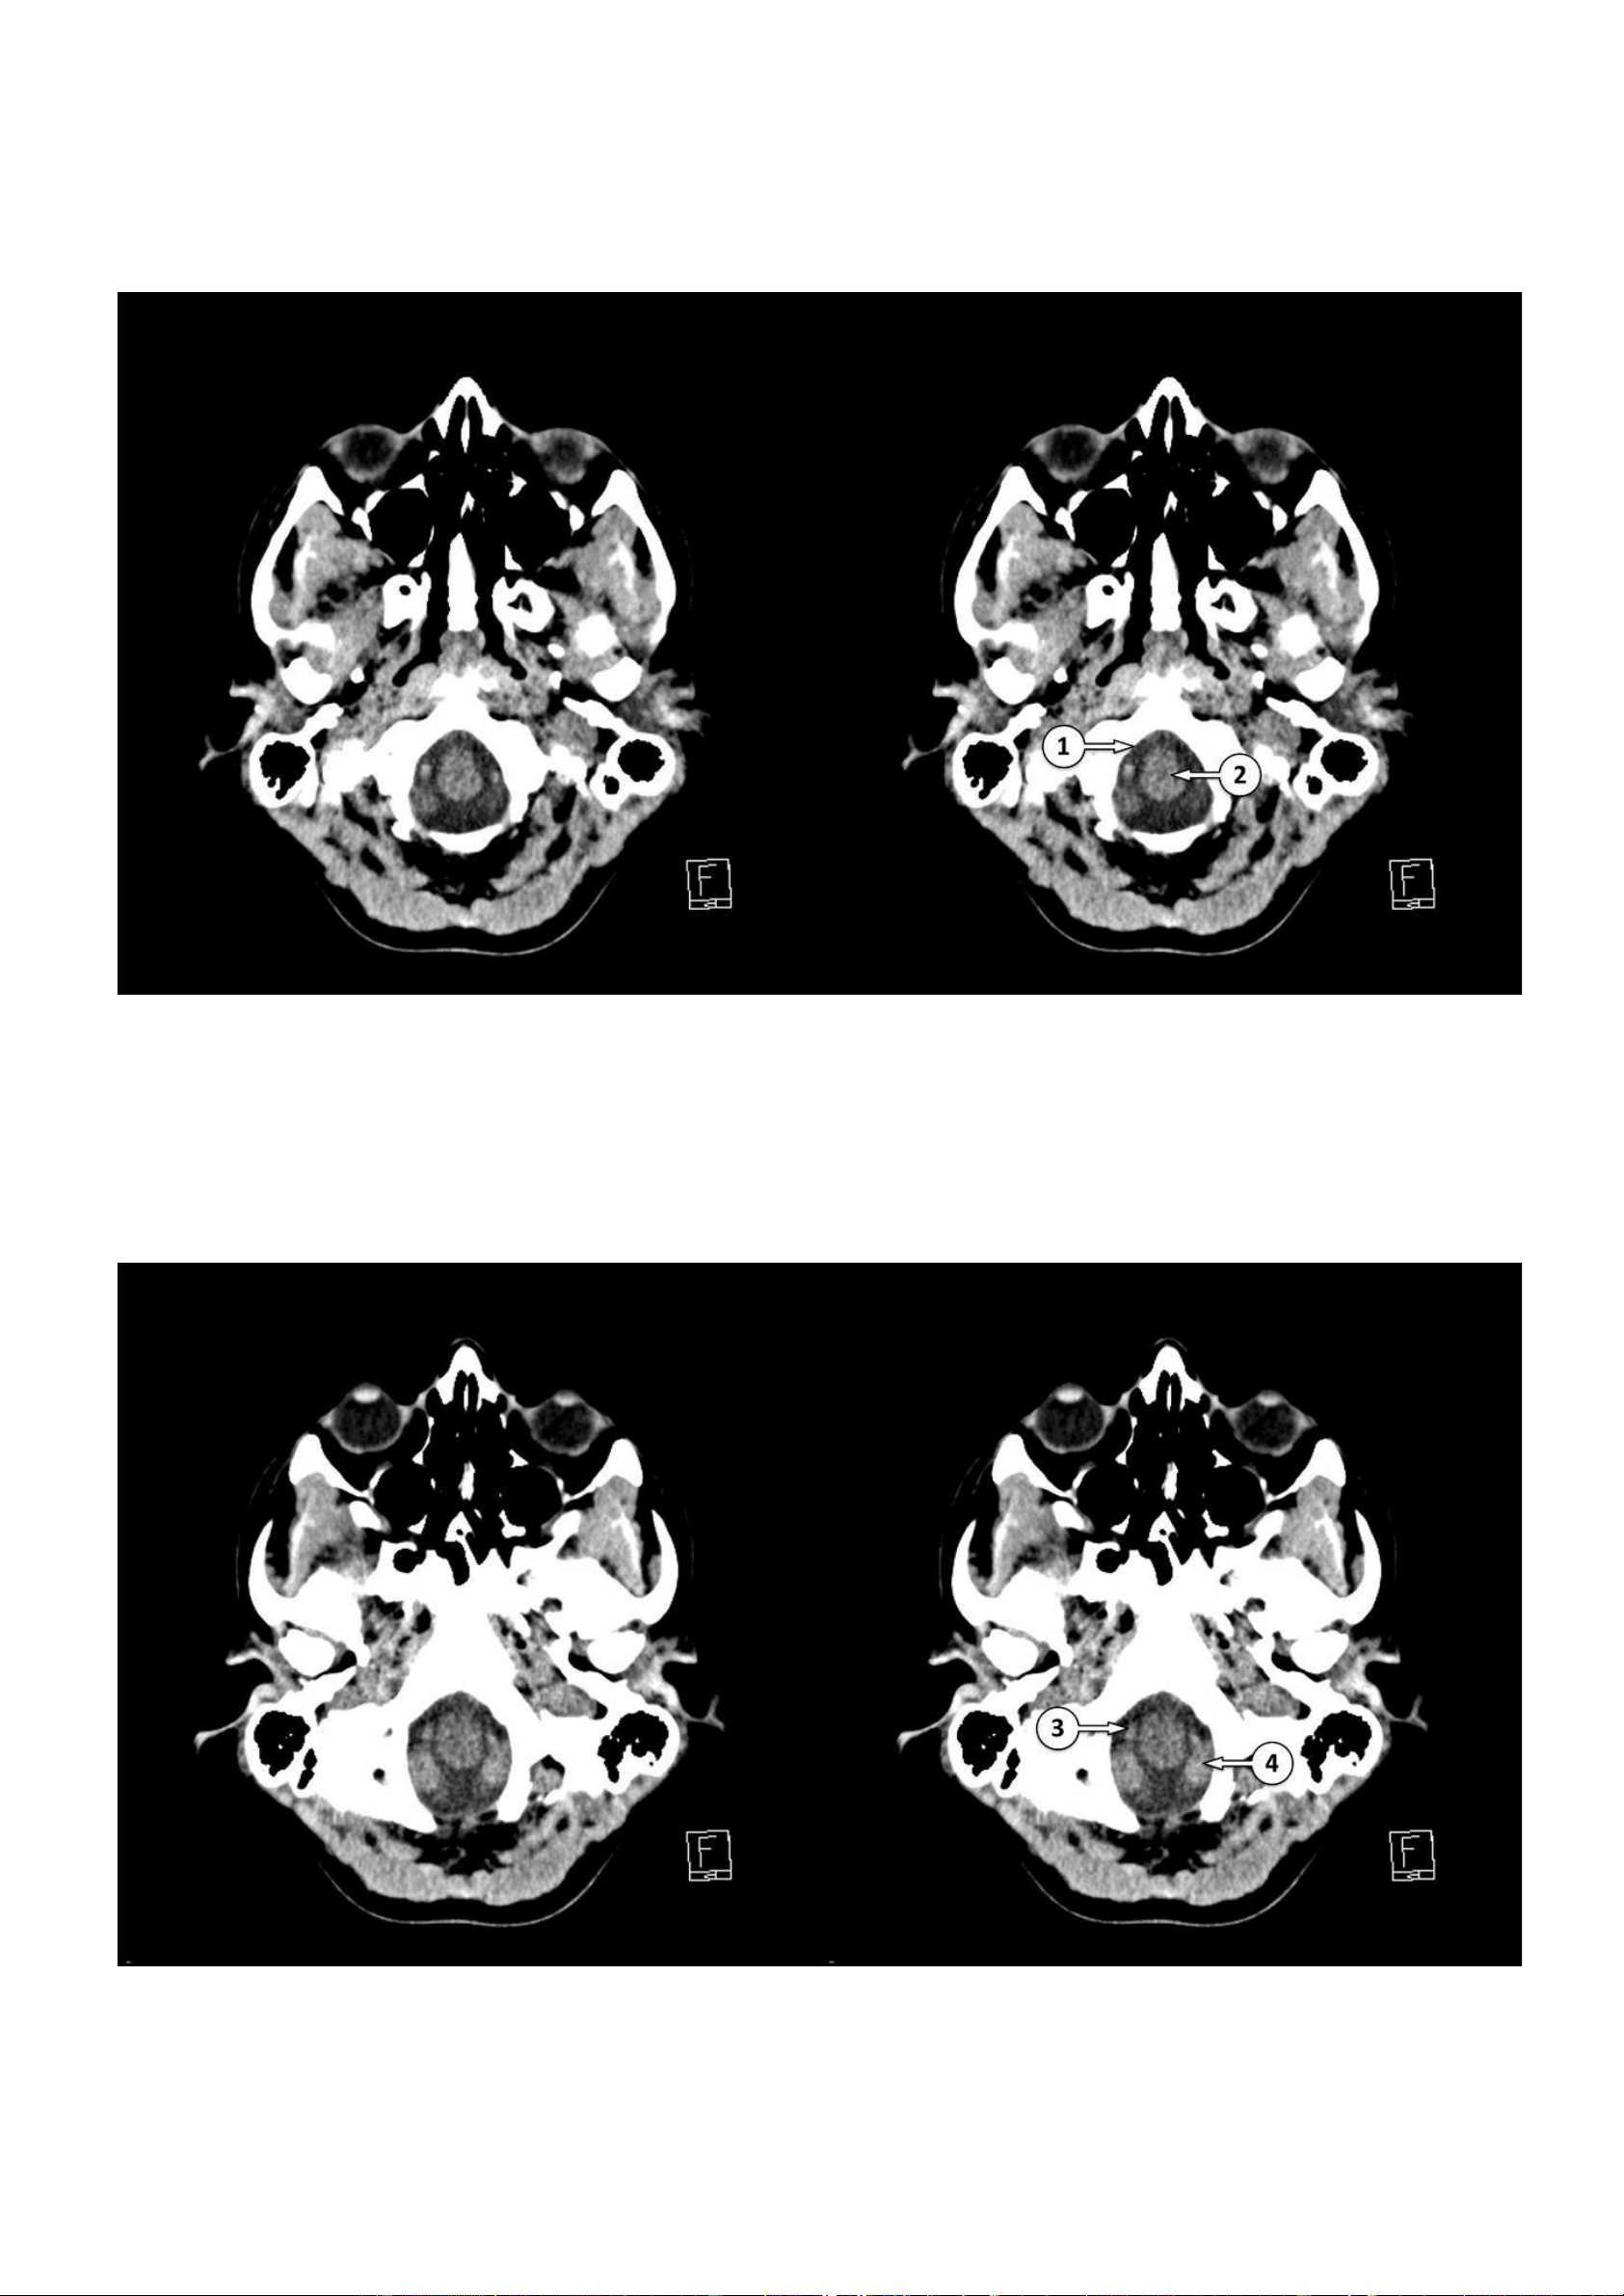

Giải phẫu cắt lớp vi tính nhu mô não ▪ Số 1: Lỗ lớn ▪ Số 2: Hành não

▪ Số 3: Động mạch đốt sống

▪ Số 4: Hạnh nhân tiểu não lOMoAR cPSD| 22014077